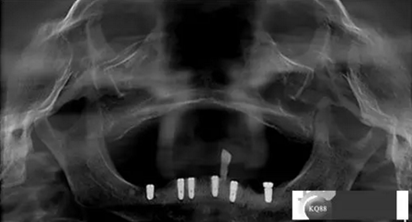

檢查:上頜無(wú)牙頜假牙穩(wěn)定性尚可,下頜3435364243殘根;33殘冠1-2度松動(dòng),其他牙齒缺失;CBCT檢查:下頜牙槽骨前牙區(qū)骨高度足,后牙區(qū)骨高度最低為8mm,骨寬度足。

1)術(shù)前檢查,拍攝臨床照片及CBCT檢查,制取活動(dòng)義齒參考模型,指導(dǎo)后期最終修復(fù)的牙齒排列

2)術(shù)前準(zhǔn)備及手術(shù)過(guò)程,測(cè)量血壓及血糖,簽種植知情同意書;嚴(yán)格遵循無(wú)菌操作,局麻下采用微創(chuàng)技術(shù)于323436分別植入osstem4.0X10,4.0X10,4.5X7; 434446分別植入osstem4.0X1O,4.0X10,4.5X7.初期穩(wěn)定性均達(dá)到了35N.CM以上;嚴(yán)密縫合,止血,種植體位點(diǎn)和方向與設(shè)計(jì)一致。